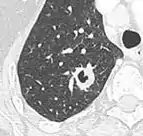

• Bubble-like lucencies in the nodule indicate cancer:[9]

Air bronchograms is defined as a pattern of air-filled bronchi on a background of airless lung, and may be seen in both benign and malignant nodules, but certain patterns thereof may help in risk stratification.[9]